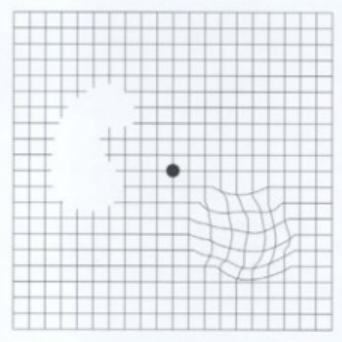

다음은 황반변성 자가진단법입니다.

위의 이미지를 30cm 이상 멀리서 봅니다.

시력검사를 하듯이 한쪽 눈을 가린 상태에서

가운데 검정색 점을 바라봅니다.

양쪽을 테스트하여 정상적으로 보이는지

자가진단을 해보시기 바랍니다.

황반변성 증상이 있을 경우에는

그림이 또렷하지 않게 보입니다.

혹은 그림의 일부가

변형되거나 왜곡되어 보입니다.